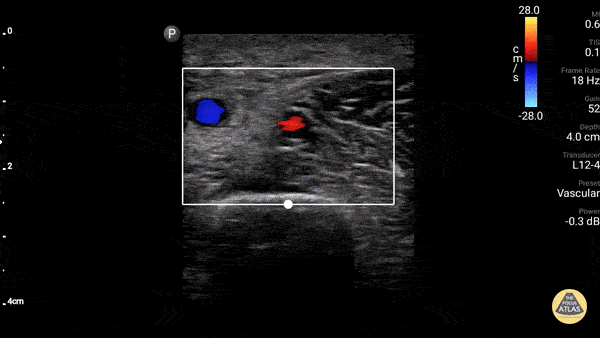

Using a high-frequency linear probe, evaluate the deep veins of the upper extremity starting just proximal to the antecubital fossa. Pulsed-wave or color flow may be applied to differentiate brachial vein from artery. Follow this distal portion of the brachial vein proximally along the axillary vein, sequentially applying and releasing gentle compression to fully collapse the vessel at 1-2cm intervals until arriving at the subclavian vein, which will be adjacent to subclavian vein and superficial to pleura.

Figure 3. Normal axillary vein and artery. Source: The POCUS Atlas, by Dr. Gordon Johnson.